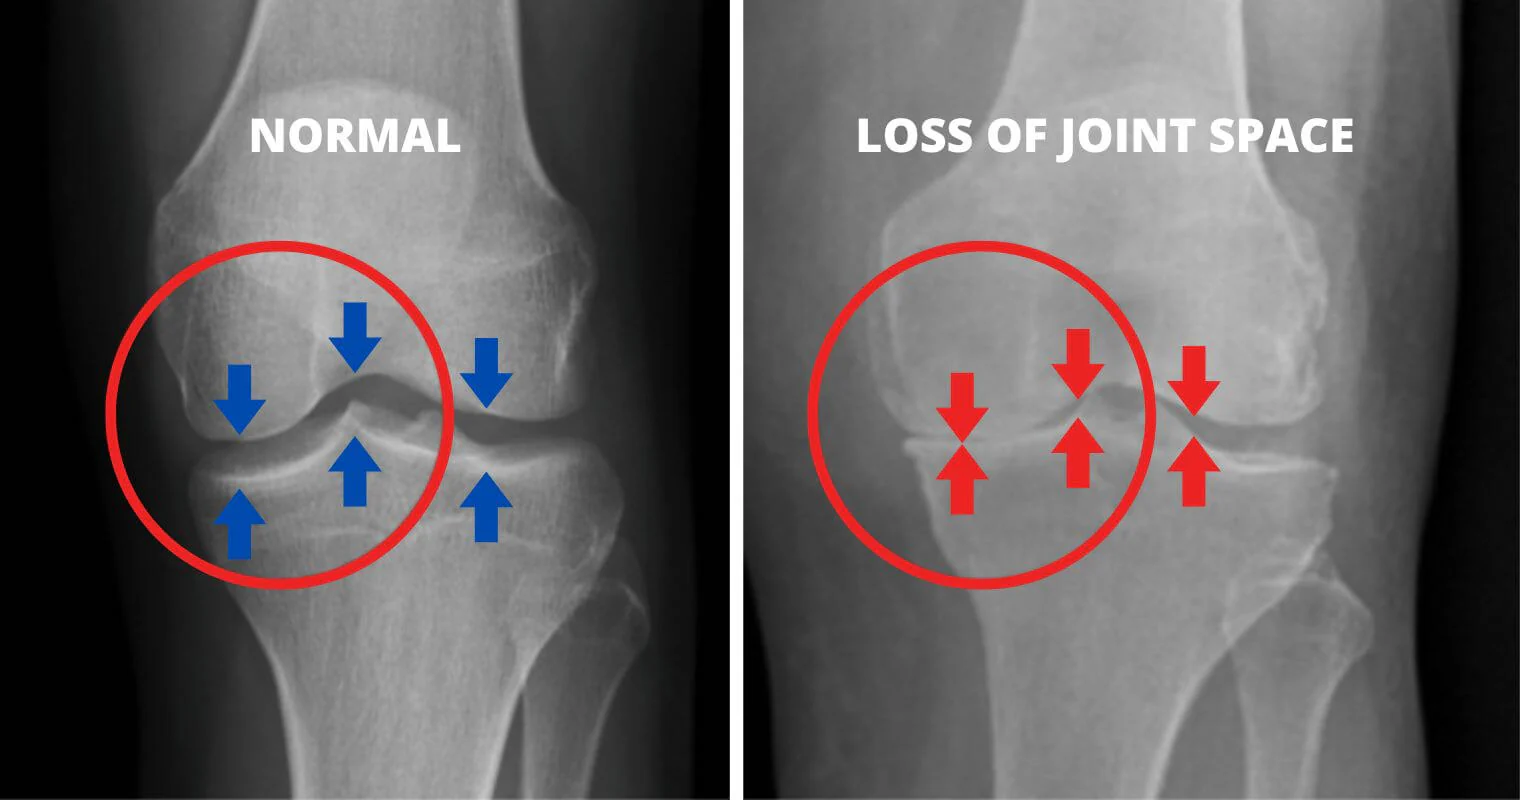

What if I told you that the knee pain and stiffness you feel are caused by the wear and tear of your cartilage, leading to uncomfortable friction?

Our knees are crucial for our mobility, and they bear the brunt of our body weight every day. They act as shock absorbers, cushioning the impact from walking, running, and other daily activities.

As the cartilage wears away over time, the bones start to rub against each other, causing intense pain and discomfort. This friction leads to discomfort, swelling, and a significant reduction in mobility.

As you age and continue to put stress on your knees, the cartilage deteriorates. And when this happens, you start experiencing severe pain due to the bones rubbing together.